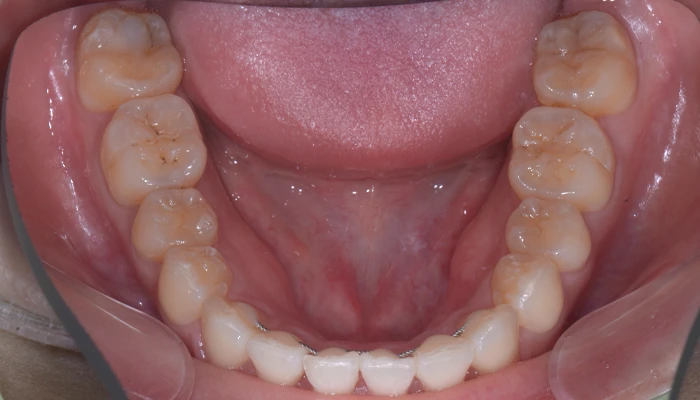

症例8. 下顎のみ部分矯正/

大臼歯近心移動

治療前

治療後

治療期間 | 18ヶ月 |

---|---|

治療費 | 15万+tax (別途調整料) |